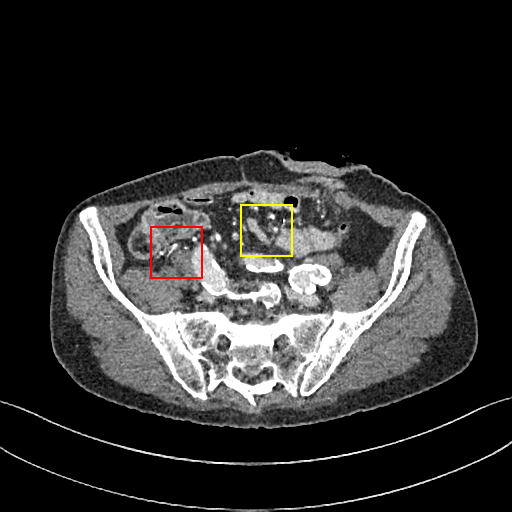

Figure 6: Visual comparison of SRCT Case 222 from the abdominal dataset. The display window is [-160, 240] HU. The restored anatomical features are shown in the red and yellow boxes. (Zoomed for visual clarity).

III-E Experimental Results on the Abdominal Dataset

We further compared the above-mentioned algorithms on the abdominal benchmark dataset. A similar trend can be observed on this dataset. Our proposed GAN-CIRCLE can preserve better anatomical informations and more clearly visualize the portal vein as shown in Fig. 6. These results demonstrate that PSNR-oriented methods (FSRCNN, ESPCN, LapSRN) can significantly suppress the noise and artifacts. However, it suffers from low image quality as judged by the human observer since it assumes that the impact of noise is independent of local image features, while the sensitivity of the Human Visual System (HVS) to noise depends on local contrast, intensity and structural variations. Fig. 6 displays the LRCT images processed by GAN-based methods (SRGAN, G-Adv, GAN-CIRCLE, GAN-CIRCLEs, and GAN-CIRCLEu) with improved structural identification. It can also observed that the GAN-based models also introduce strong noise into results. For example, there exist tiny artifacts on the results of GAN-CIRCLEu. As the SR results shown in Fig. 6, our proposed approaches (GAN-CIRCLE, GAN-CIRCLEs) are capable of retaining high-frequency details to reconstruct more realistic images with relatively lower noise compared with the other GAN-based methods (G-Adv, SRGAN). Table II show that G-Fwd achieves the best performance in PSNR. Our proposed methods GAN-CIRCLE and GAN-CIRCLEs both obtain the pleasing results in terms of SSIM and IFC. In other words, the results show that the proposed GAN-CIRCLE and GAN-CIRCLEs generate more visually pleasant results with sharper edges on the abdominal dataset than the competing state-of-the-art methods.